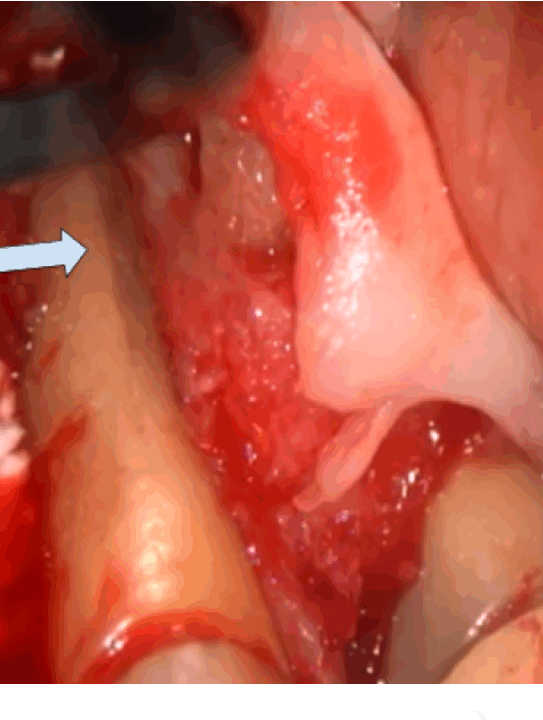

歯茎を開いてみたら、ヒビが見られた歯。